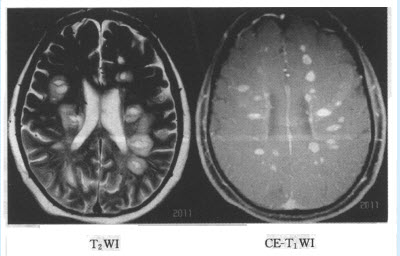

患者,女,58岁。反应迟钝、走路不稳5天,影像学检查如下图。

[单选题]患者,女,58岁。反应迟钝、走路不稳5天,影像学检查如下图。首先诊断()A . 皮层下动脉硬化性脑病B . 转移瘤C . 免疫有关脊髓炎D . 脑炎E . 多发性硬化

[单选题]患者,女,58岁。反应迟钝、走路不稳5天,影像学检查如下图。首先诊断A.皮层下动脉硬化性脑病B.转移瘤C.免疫有关脊髓炎D.脑炎E.多发性硬化

[单选题]多发性硬化影像学改变常出现A.MRI无明显异常B.CT显示一侧大脑基底节高密度病灶,伴有病灶周围低密度带C.CT显示累及大皮质和白质的大片楔状低密度病灶D.MRI显示额颞叶为主的广泛性脑萎缩E.CT显示脑室附近白质多发性低密度灶